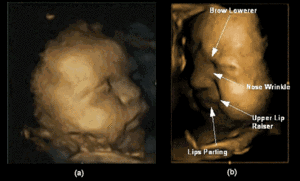

(VTC News) - Những tấm hình ấn tượng của em bé chưa chào đời nhăn nhó mặt mày trong khi người mẹ đang vật vã với những cơn đau đẻ.